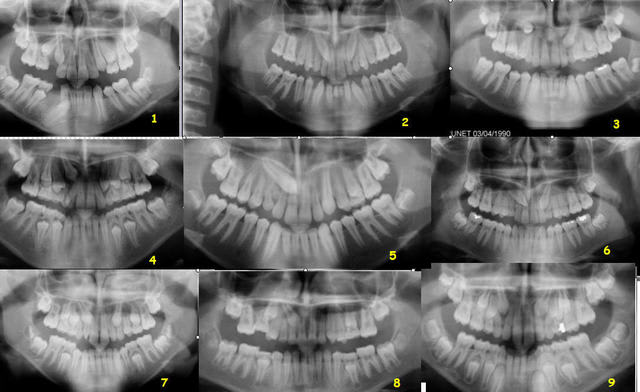

OK, faisons un "quiz".

De 1 à 9 :

1 - 13 V ou P ? - 43 V ou P ?

2 - 13 V ou P ? - 23 V ou P ?

etc.

A toi, alexlop. Tu peux demander de l'aide aux autres, bien entendu.

Daniel

mais pour le jeu:

1 - 13 V et 43 L

2- 13 et 23 couronne V

3- 13 et 23 P

4 - 13 P

5- 13 P

6- 13 23 P

7- 13 P 23 V

8- 13 P

9- 13 23 P

alors ?

Pour la n°1, 43 est donc vestibulaire.

Il y a 3 autres erreurs dans cette liste.

Quelles sont-elles ?